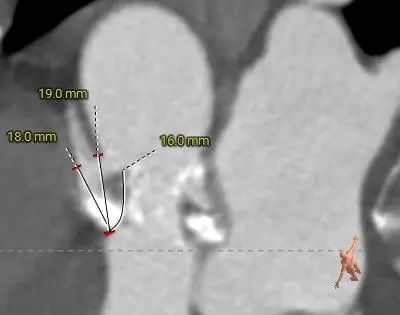

冠脉开口高度可,左冠切线角度测量瓣叶长于LCA开口下缘到根部距离

LEFT CORONARY

RIGHT CORONARY

LCA&LEAFLET

RCA&LEAFLET